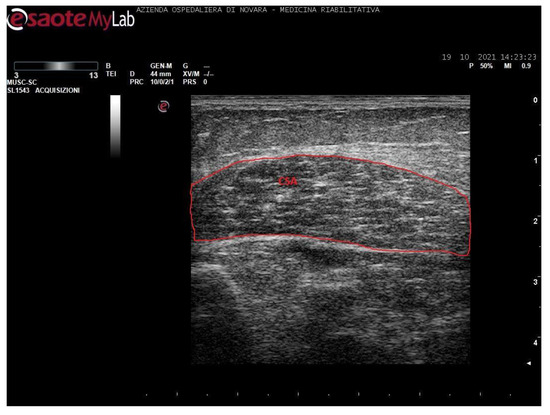

We acquired images of the medial gastrocnemius (MG) and soleus (SOL). Images were processed through the software ImageJ (National Institutes of Health, USA) in order to measure the muscle thickness (MT, cm), the cross-sectional area (CSA, cm2), the pennation angle (α, °), and the mean gray value (MGV, range 0-255). MGV was assessed considering the whole muscle longitudinal section as region of interest (ROI). The gray scale spreads from 0 (black) to 255 (white).

Measurements were taken as shown in Figure 1, Figure 2, Figure 3 and Figure 4.

Figure 1. Ultrasound image of medial gastrocnemius in transversal section. In red: cross-sectional area (CSA).